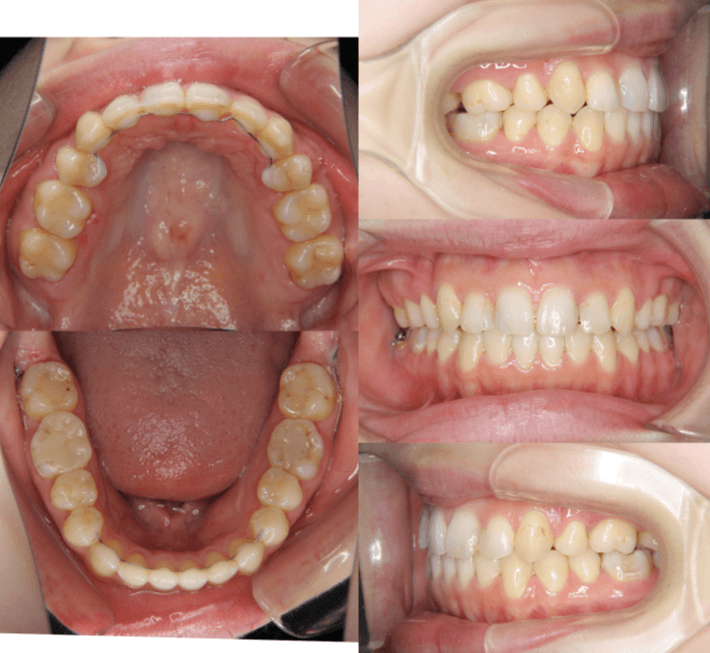

咬み合わせが逆であること(反対咬合)が気になる

| 年齢・性別 | 15歳 女性 |

|---|---|

| 主訴 | 咬み合わせが逆であること(反対咬合)を気にされて来院された女性。見た目や機能面の改善を希望されていました。 |

| 治療期間・回数 | 4年4ヶ月・28回 |

| 費用 | 900,000円 |